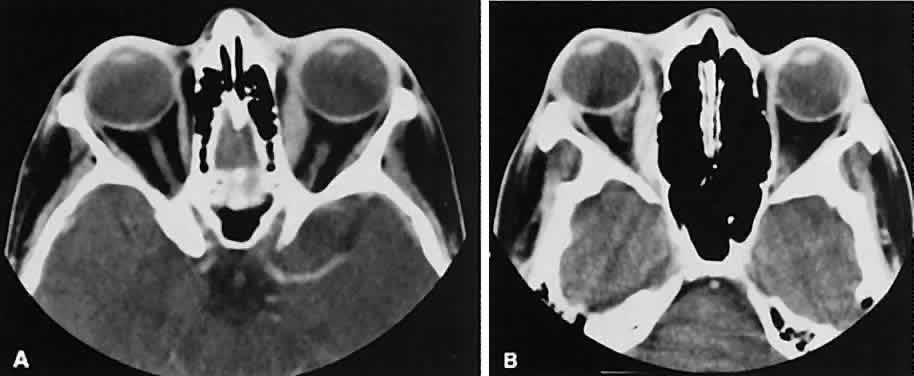

The edema and inflammatory infiltrate that accompany infections are indistinguishable from that associated with orbital inflammations. The presence of sinus disease, however, is a more constant feature with infections, because the sinus represents the infectious nidus in most cases (Fig. 9). In addition to the frequent appearance of sinus disease, the adjacent EOM is invariably enlarged. Less often, orbital infections may be transmitted through the blood, related to a retained foreign body, or spread from the lids. Chandler and colleagues47 classified orbital infections into five groups. Group 1 (preseptal cellulitis) represents inflammatory edema and reflects congestion of venous outflow. Group 2 has actual orbital infiltration/edema with mass effects and functional deficits. Group 3 includes patients with subperiosteal abscesses. Most of these dome-shaped subperiosteal abscesses are located along the medial wall. Group 4 includes patients with orbital abscesses who may display a ring-enhancing lesion with mass effect. Group 5 represents intracranial extension of the inflammation into the cavernous sinus or sinuses, which appear engorged and opacified.

Fig. 9. Orbital cellulitis. A. Axial view shows a subperiosteal soft-tissue mass displacing the medial rectus muscle. The ethmoidal sinus is opacified secondary to inflammatory disease, which invariably precedes the orbital inflammation. B. Coronal view further shows the subperiosteal and ethmoidal sinus inflammation. Inflammation changes also are seen in each maxillary sinus.